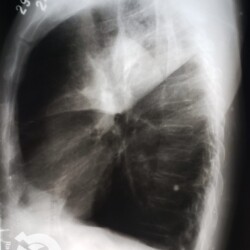

Os agentes etiológicos infecciosos são variados (bactérias, vírus, fungos, parasitas…), mas o que ocorre nos pulmões durante uma infecção por qualquer tipo de agente é a substituição do ar alveolar por secreção (pus, muco, eventualmente sangue ou necrose…) e com isso a manifestação radiográfica vai ser a mesma já que todas estas secreções apresentam a mesma densidade radiográfica: partes moles.

E o nome dado a esta alteração radiográfica que corresponde à substituição do ar alveolar por líquido é a consolidação alveolar.

Uma consolidação alveolar é, por definição, uma opacidade (imagem densa, branquinha) homogênea ou às vezes heterogênea (pela presença de calcificações ou cavidades), de limites mal definidos, exceto quando toca a pleura da parede ou das cissuras pulmonares. É um termo usado tanto em radiografia, como em tomografia computadorizada. Na tomografia, um outro termo é usado: vidro fosco, que é uma opacidade (branquinha mas não tanto como a consolidação), que borra o pulmão mas deixa ver os vasos de permeio (igual bigode de adolescente: dá pra ver todo o fundo).

Nós vamos mostrar aqui um pequeno apanhado de pneumonias de variados agentes, em diversos segmentos e lobos pulmonares, com extensões variadas. O objetivo é identificar o padrão radiológico de consolidação alveolar e não determinar o agente infeccioso, isso vai ser assunto para mais adiante. Aliás já antecipo que é fundamental saber localizar a lesão, porque alguns destes bichos gostam de determinados segmentos, alguns tumores também têm as suas preferências, então localização é fundamental. Se localização não fosse importante, um apartamento na beira do mar sairia o mesmo preço de um apartamento de frente pra BR-101, concordam?

Seguem alguns dos nossos casos de pneumonia para vocês treinarem os olhos e não se apavorarem nos plantões.